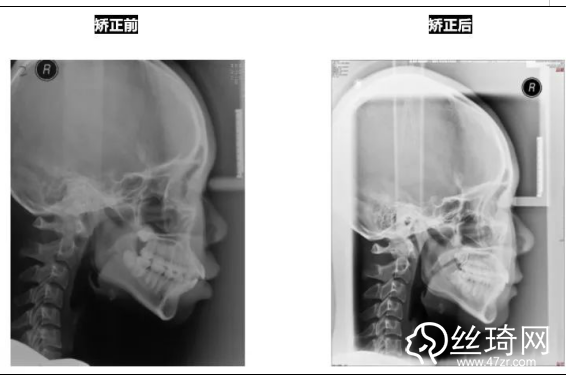

* 影像學(xué)檢查分析(以及調(diào)節(jié)前后影像對比):

全景片:

頭顱側(cè)位片:

前后頭影測量結(jié)果對比: